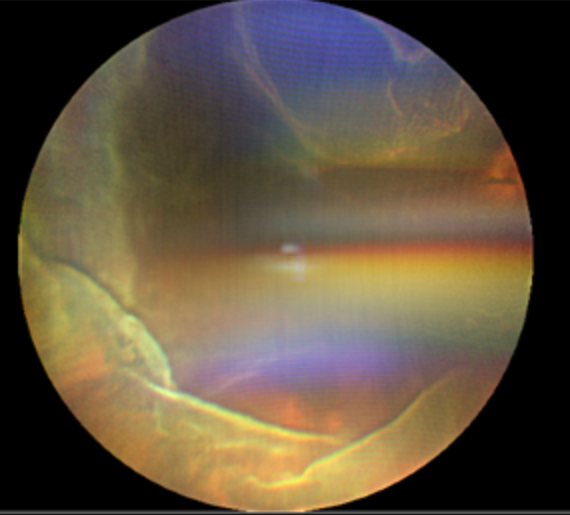

顧名思義,這個病至少包含兩個表現(xiàn):視網(wǎng)膜脫離和脈絡膜脫離。1. 視網(wǎng)膜脫離:視網(wǎng)膜是眼球最內(nèi)層的一層透明薄膜,相當于相機的底片。當它因為視網(wǎng)膜裂孔從依附的壁上“脫下來”時,就形成了孔源性視網(wǎng)膜脫離。患者通常會感到眼前有黑影遮擋,有閃光感、飛蚊癥,脫離累及視網(wǎng)膜最重要的結(jié)構(gòu)——黃斑中心凹時,視力會急劇下降。2. 脈絡膜脫離: 脈絡膜是位于視網(wǎng)膜和眼白(鞏膜)之間的一層富含血管和色素的組織,負責為視網(wǎng)膜提供營養(yǎng)和氧氣。當它因為眼壓過低或炎癥等原因而脫離時,眼底會表現(xiàn)為棕色的“鼓包樣”隆起。當這兩種嚴重的情況同時發(fā)生,就形成了脈絡膜脫離型視網(wǎng)膜脫離。它不僅僅是“底片”脫落,更是“底片”和滋養(yǎng)它的“土壤”一起大面積脫離,對視力構(gòu)成嚴重威脅。

治療:一旦確診,應盡早進行手術(shù)。術(shù)前術(shù)后需要加強抗炎治療。手術(shù)方式: 通常需要進行復雜的玻璃體切割手術(shù),必要時聯(lián)合鞏膜環(huán)扎術(shù),術(shù)中會使用激光封閉視網(wǎng)膜裂孔,并向眼內(nèi)注入特殊的氣體或硅油來頂壓視網(wǎng)膜和脈絡膜,為暫時復位的視網(wǎng)膜和脈絡膜提供支撐,幫助病情康復。